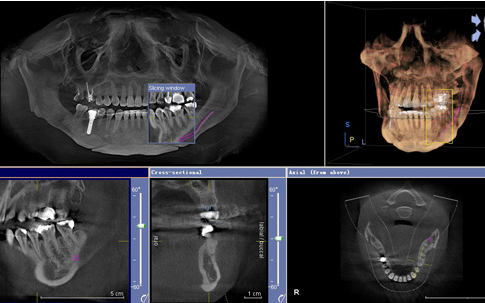

唯美即刻种植牙针对牙槽骨情况好的患者可以实现即刻种植、即刻修复,通俗

来讲就是种完马上安装牙冠,马上有牙齿,而不需要像传统种植牙埋入3个月后割

开做二期修复,二期修复2个星期后拆线,拆完线再等一个星期才能带牙。